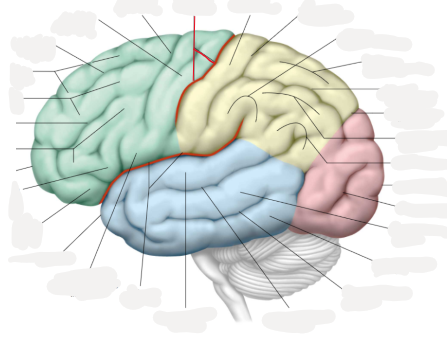

lobus frontalis

lobus parietalis

lobus occipitalis

lobus temporalis

insula

gyrus precentralis

gyrus postcentralis

sulcus centralis

sulcus lateralis